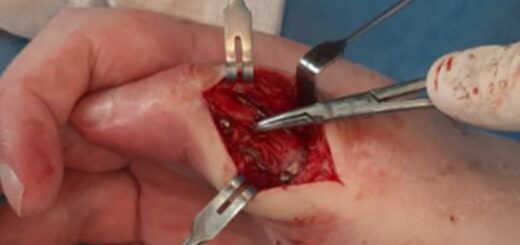

During the operation, conduction anesthesia was used. The patient’s position was supine with the arm on the bedside counter. After preparing the surgical field, a hemostatic pneumatic tourniquet was applied at the level of the middle third of the humerus. Surgical approach to the scaphoid bone was carried out from a 4–5 cm long incision along the anterior surface of the forearm, using the flexor carpi radialis (FCR) as an external landmark. After making the incision, the tendon was moved to the side for exposure of the capsule of the wrist joint and for examination of the articular surfaces of the distal radius and scaphoid bones (Fig. 1). Next, resection of the scaphoid bone was performed. To prevent impingement syndrome, resection of the styloid process of the radius was performed. Then, through an additional dorsal approach 4–5 cm long, the retinaculum extensorum was exposed and the 5th canal of extensors was opened. The extensor tendons of the fifth finger were moved to the side, the wrist capsule was incised along the dorsal radiocarpal ligament (DRC) (Fig. 2), and the distal radius and midcarpal joint were examined to ensure the integrity of the lunate fossa of the radius and capitate bones.

| Fig. 1 Palmar approach | Fig. 2 Dorsal approach to the wrist |